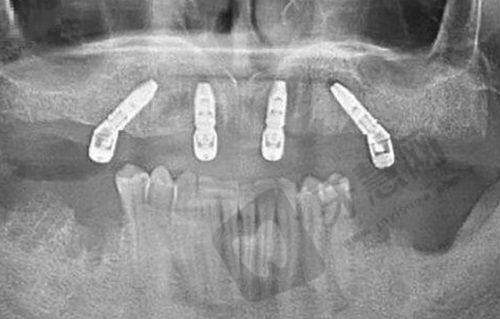

特色项目:数字化缺失牙种植修复、即刻种植、半口全口All-on-4种植技术、微创拔牙、高难度阻生齿拔除。

特色项目:种植牙(包括微创种植)、个性化牙齿矫正、口腔综合治疗。

特色项目:种植牙、牙齿矫正、口腔综合治疗。